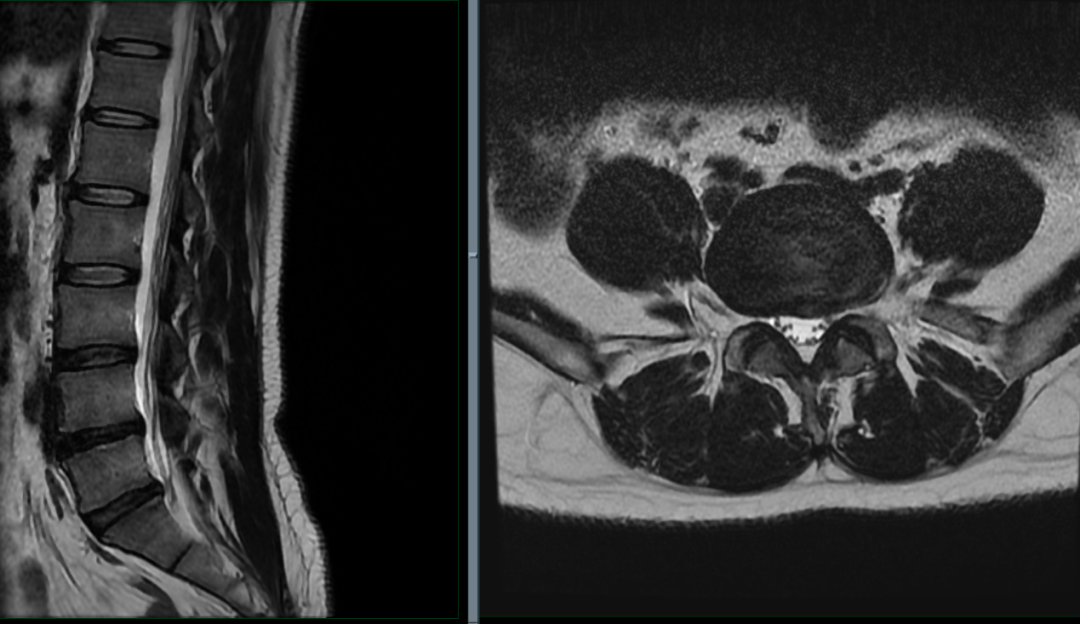

L4/5 水平:

L4/5 变性,突出(中央型)